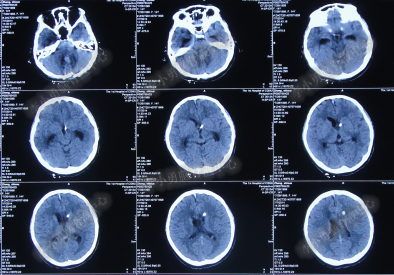

患者因恶心、呕吐伴头痛头晕,自行服药后无法自行缓解,于2014年5月29日就诊位于重庆的著名的三甲肿瘤医院,查全脑CTA和CT后诊断为“小脑蚓部占位伴幕上脑积水”(图-1、图-2)。

图-1:2014年5月29日全脑CTA